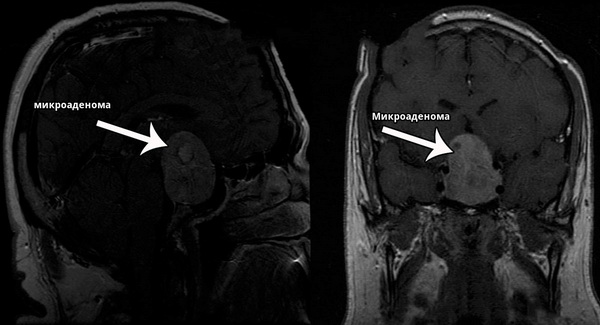

Магниторезонансная томография позволяет выявить аденомы размером от 2 мм. Но томограмма лишь показывает наличие аденомы. Чтобы установить тип аденомы и определить необходимое лечение, нужно также дополнительное обследование.

Даже если все симптомы указывают на наличие опухоли в гипофизе, требуется проведение МРТ и компьютерной томографии для определения места расположения опухоли и её размеров. При диагностике микроаденом из-за их небольших размеров рентгеноскопические исследования обычно малоэффективны.

Микроаденома гипофиза — это доброкачественная опухоль, размер которой не превышает 10 мм. Она может вызывать различные гормональные нарушения в организме. Диагностика микроаденомы обычно включает магнитно-резонансную томографию (МРТ) для визуализации опухоли, а также анализы крови на уровень гормонов, чтобы определить, влияет ли опухоль на гормональный баланс.